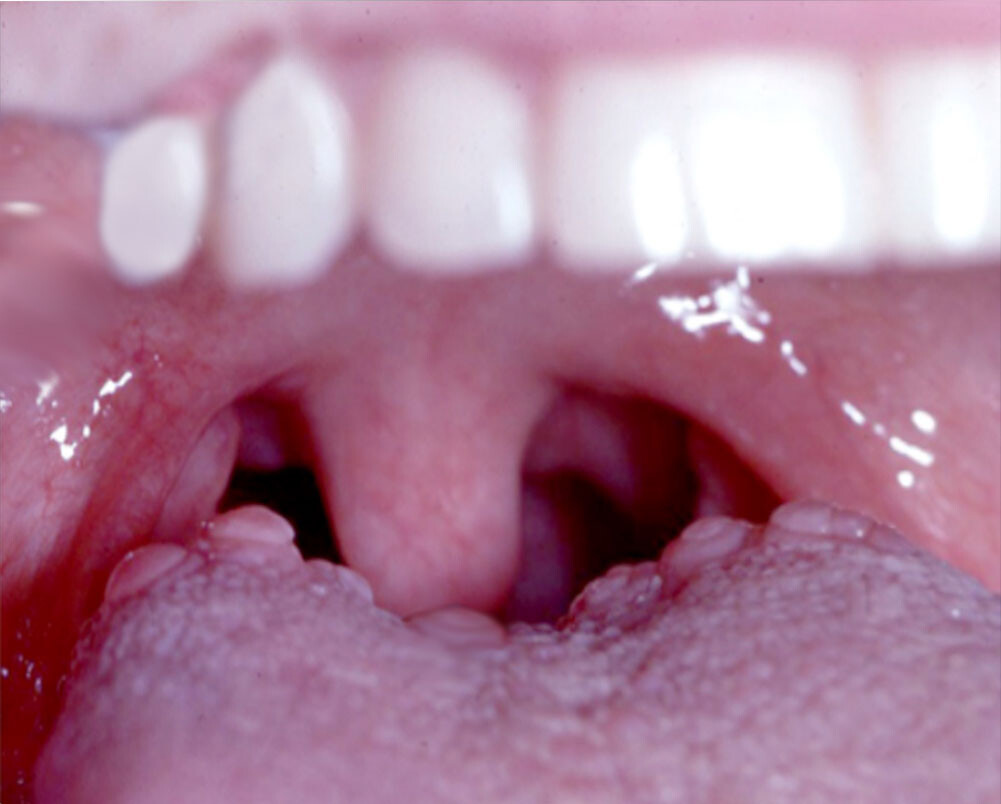

Oral squamous papilloma. This is a benign mass that appears on the border of the tongue. They are often attributed to the human papillomavirus (HPV). According to a study in the International Journal of Scientific Reports, the best way to remove them is through surgery. They’re also unlikely to recur, except in immunocompromised patients.

The tongue is made up of muscles and the surface is covered with a mucous membrane. Typically, small bumps (also known as papillae) cover the surface of the back part of your tongue. Between the papillae are your taste buds that help you taste foods. Usually, these papillae are pretty unnoticeable. But sometimes, they become enlarged and can cause you pain. This can happen for many reasons.